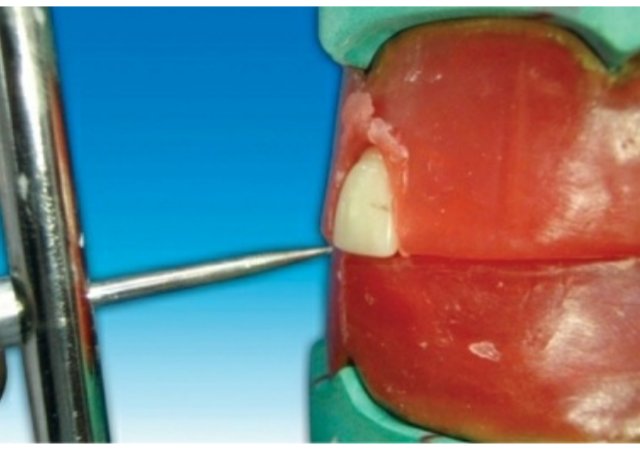

Placement of the maxillary central incisor in relation to all three planes.

🔻The long axis of the central incisor (the blue line) is positioned parallel to the

vertical axis (the red line) when viewed from the front

🔻The incisal edge of the maxillary central incisor is positioned in line with the

anterior occlusal plane . The central pin of the articulator will point the mesioincisal line edge of the central incisor.

🔻The central pin of the articulator will

point the mesioincisal line edge of the central incisor.

When viewed from:

Front: Long axis parallel towards the vertical axis.

Side: Slopes labially about 15 degrees.

Occlusal plane: Incisal edge is in contact with occlusal plane